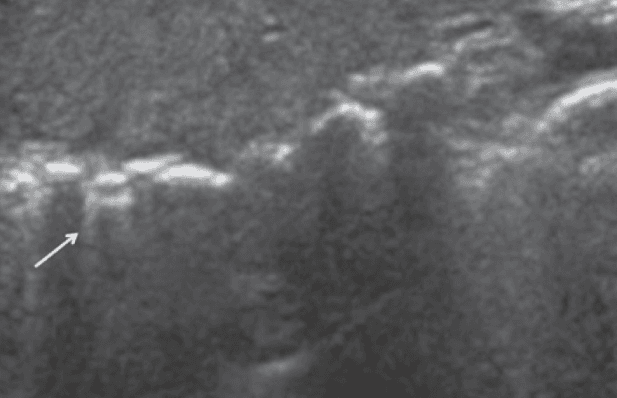

Z lines are hyperechoic lines extending from the pleural line that can sometimes be mistaken for B line but are a common finding in normal lungs. There is no clinical significance to Z lines.

E lines are hyperechoic lines originating from air in the subcutaneous tissue that can sometimes be mistaken for B lines. One important feature of E lines is that they do not originate from the pleural line. Their presence may obscure adequate visualization of the pleural line.